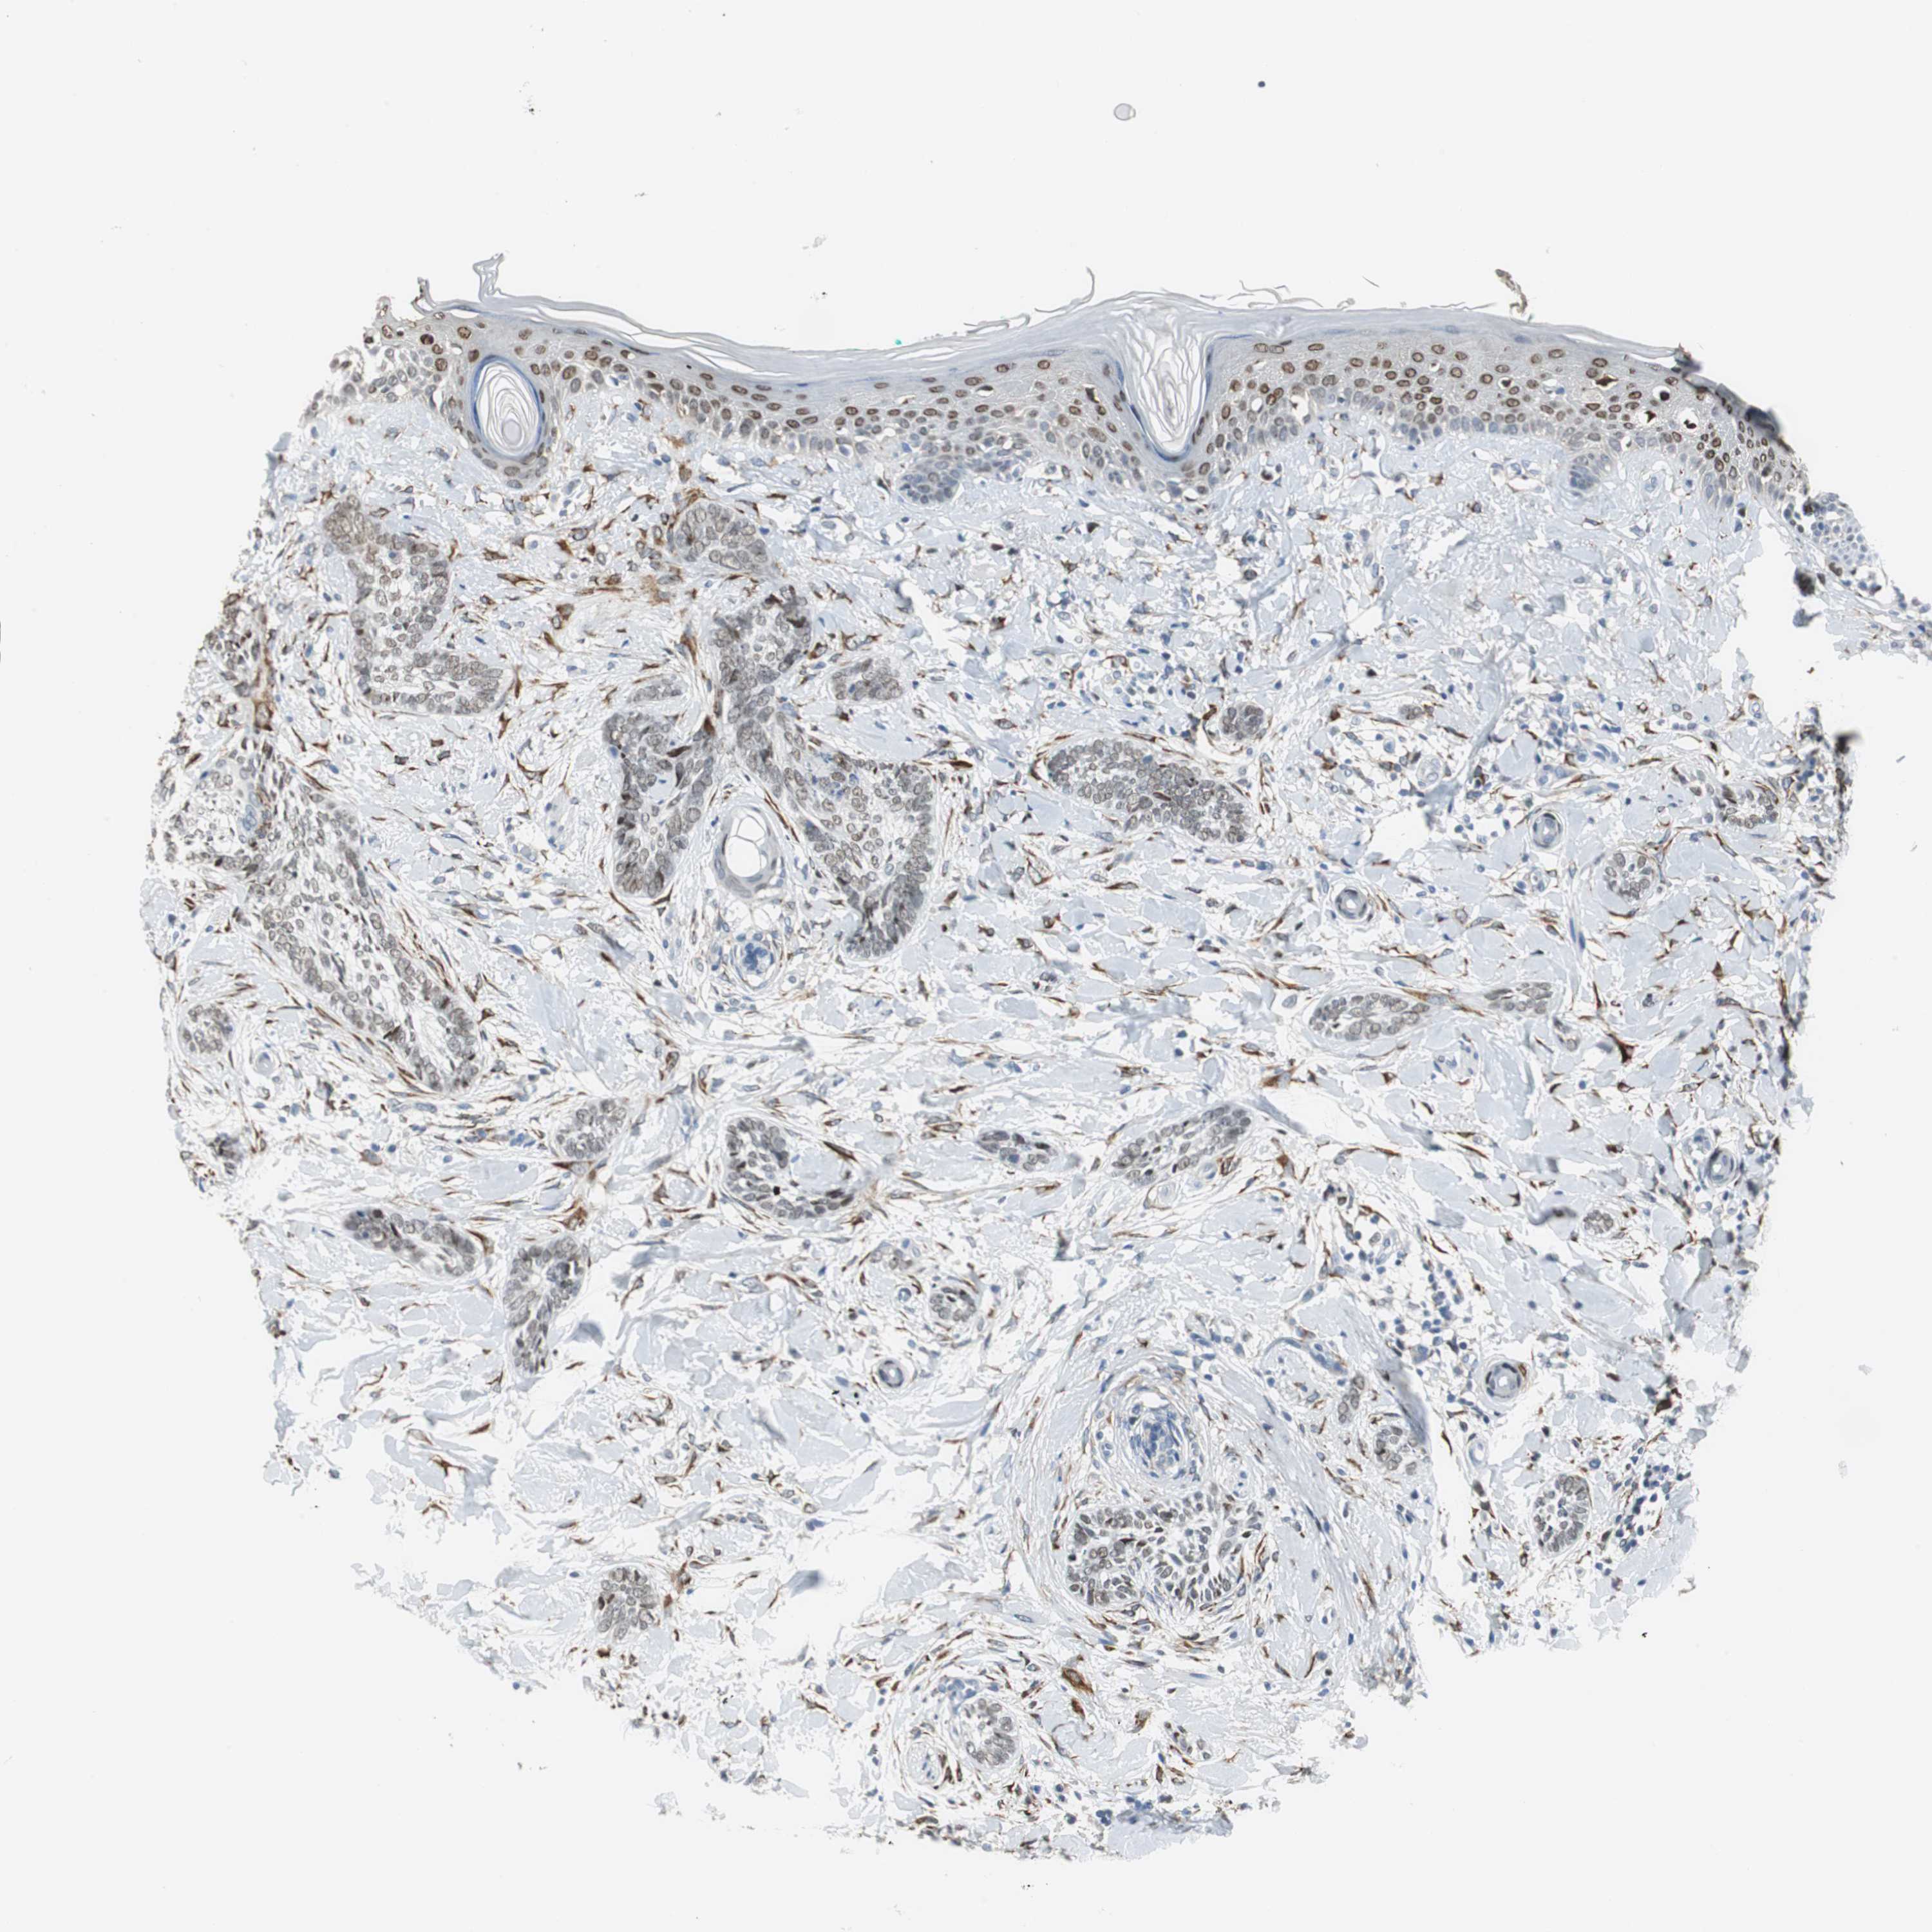

SKIN CANCER - Protein expressioni

A mouse-over function shows sample information and annotation data. Click on an image to view it in a full screen mode. Samples can be filtered based on level of antibody staining by selecting one or several of the following categories: high, medium, low and not detected. The assay and annotation is described here.

Antibody stainingi

Antibody staining in the annotated cell types in the current human tissue is reported as not detected, low, medium, or high, based on conventional immunohistochemistry profiling in selected tissues. This score is based on the combination of the staining intensity and fraction of stained cells.

Each image is clickable and will lead to virtual microscopy that enables deeper exploration of all samples and also displays staining intensity scores, fraction scores and subcellular localization as well as patient and tissue information for each sample.

Antibody HPA006465

Staining

Medium

Intensity

Moderate

Quantity

75%-25%

Location

Cytoplasmic/membranous

Basal cell carcinoma